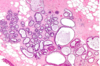

normal placenta

first trimester chorionic villi: central stroma surrounded by two layers of epithelium

double arrow (outer layer): syncytiotrophoblasts

single arrow (inner layer): cytotrophoblasts

left: first trimester

right: 3rd trimester (increased vascularity)

cells: outer: syncytiotrophoblasts; inner: cytotrophoblasts